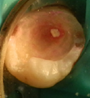

En 2011 concurre paciente de sexo masculino, de 22 años, por caries profunda en pieza 38. Radiográficamente se destaca la cercanía de la cavidad cariosa con respecto a la amplia cámara pulpar (Fig. 3a). Se diagnostica CPPA, luego de eliminar la dentina necrótica reblandecida superficial con cucharita de dentina y verificar su vitalidad con test de fresado. En la evaluación dentinaria se constata dentina de color marrón, blanda y húmeda. Se planifica Técnica de eliminación de caries en etapas. La Fig.3b muestra eliminación total de caries de paredes laterales con control colorimétrico sin tocar la pared pulpar.